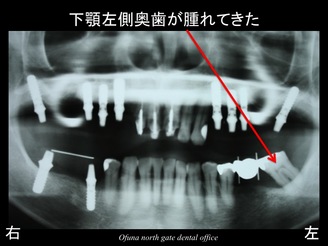

この時点で下顎左側の奥歯が腫れてきました。

初診時にすでにこの部分は、抜歯が必要なことをお話してあったため、この後抜歯となりました。